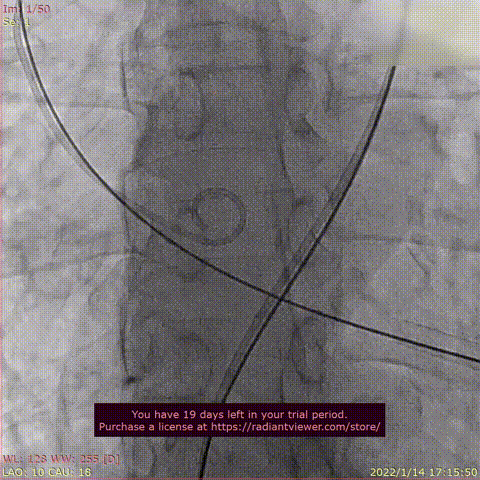

术后DSA影像图